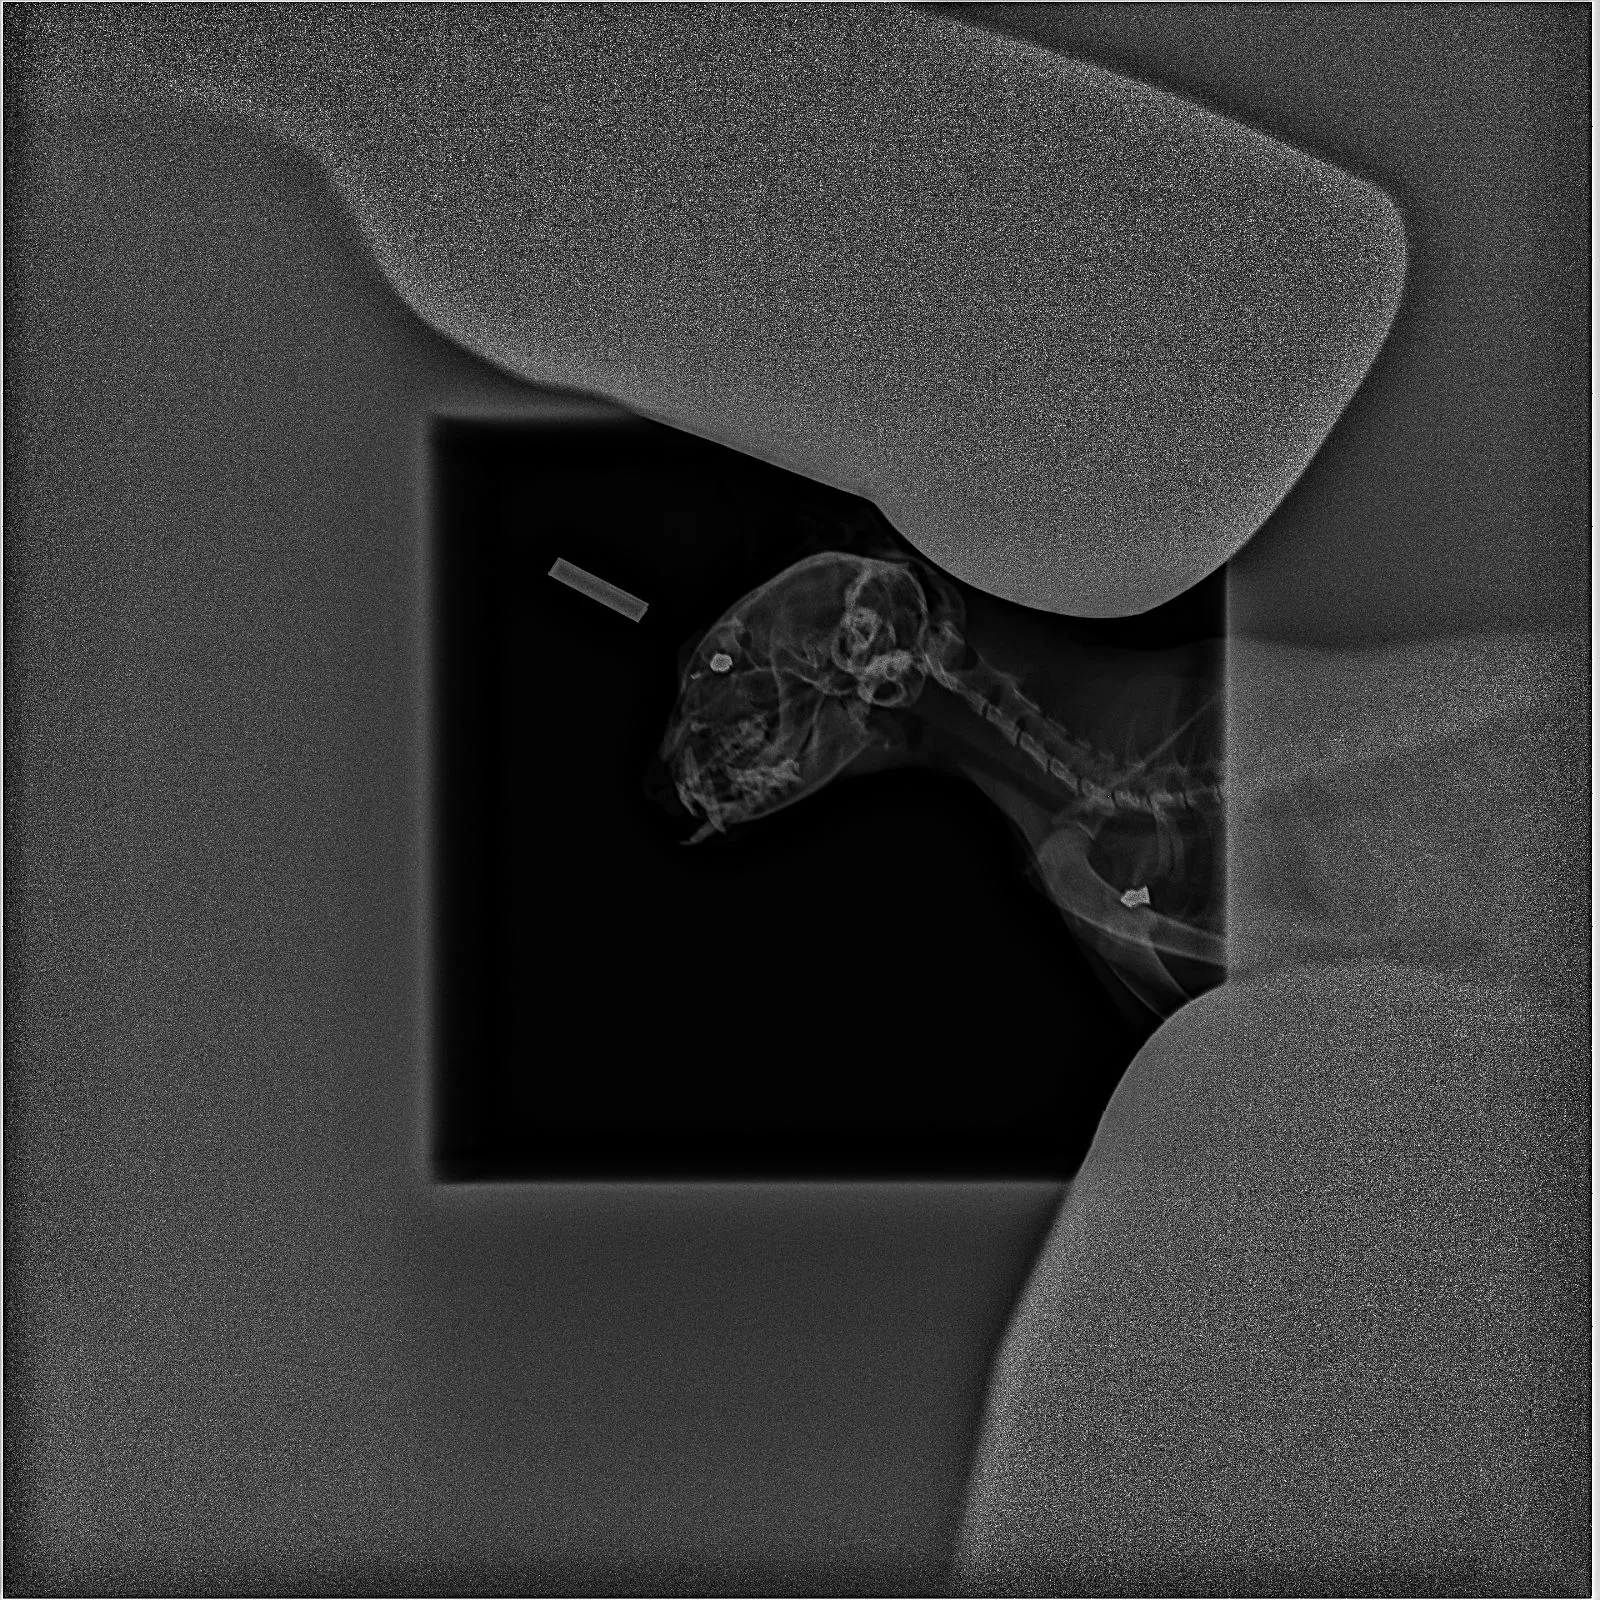

Ha sido encontrada con un cambio trascendental en su existencia: del carácter mimoso de antaño ha pasado a la desconfianza total. En la radiografía se aprecia que su cuerpo aloja dos perdigones, uno junto al ojo y otro en el omóplato de la patita izquierda. Tiene el fémur roto y, presumiblemente por una patada en la cara, un colmillo asoma fuera de la boca. Además, su anca trasera derecha revela un mordisco, muy probablemente de perro.